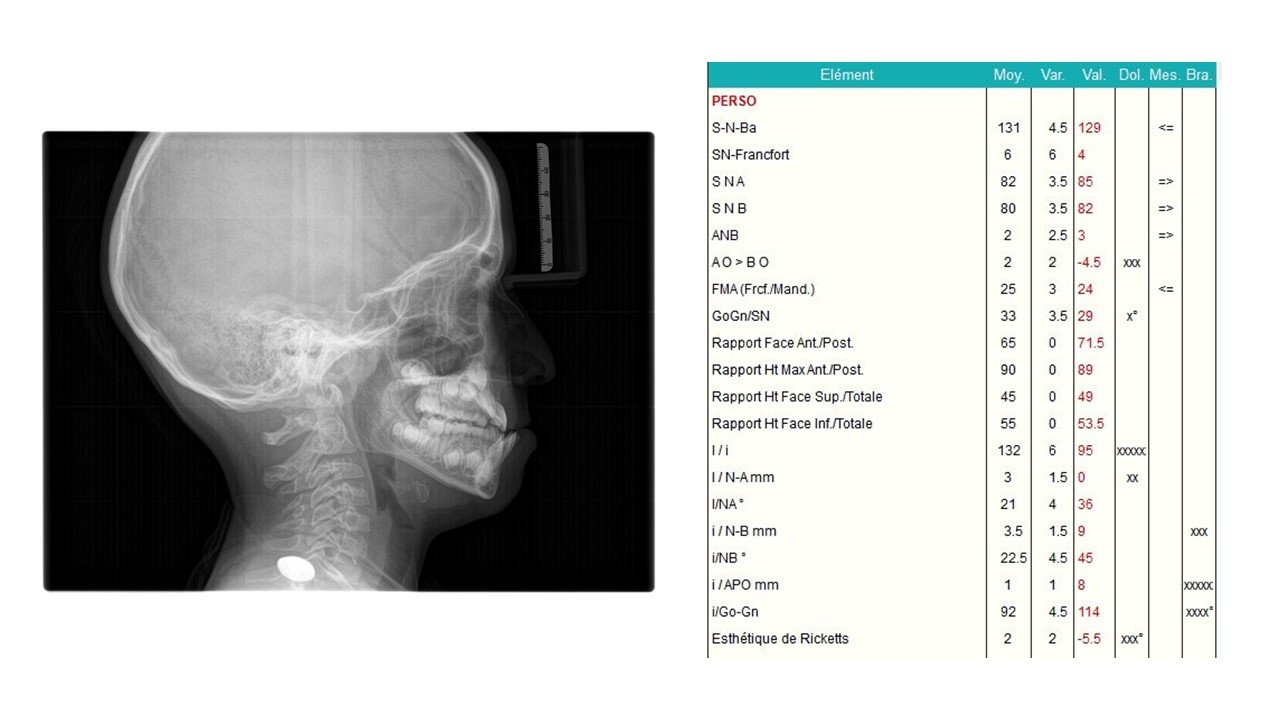

La Classe III Squelettiques

Les classes III squelettiques sont l’expression d’une orientation pathologique du plan occlusal et de la croissance faciale.

L’orthodontie systémique permet d’appréhender cette pathologie par l’analyse des latéralités mandibulaires.

Le traitement qui en découle est donc fonctionnel et stable car il permet non pas seulement une protraction du maxillaire mais une réorientation complète de celui-ci. Cette prise en charge permet de retrouver une proprioception maximale du prémaxillaire dans la mastication, gage de stabilité à long terme.